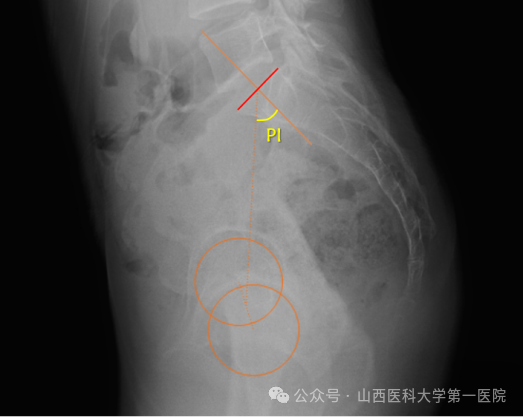

9. 骨盆入射角(PI)

骨盆入射角定义为经骶骨上终板中点做垂直于骶骨上终板的垂线,再经骶骨上终板中点与双侧股骨头中心连线中点作直线,两直线的交角。它是一个解剖学参数,取决于骨盆形状,成年后固定,与脊柱曲线关系密切,且不受姿势的影响,是调节脊柱-骨盆矢状面平衡的重要因素。PI值大小反映了骨盆对矢状位失衡的代偿能力,PT值越大,理论上骨盆对矢状位失衡的代偿能力越强。

10.骨盆倾斜角(PT)

骨盆倾斜定义为骶骨上终板中点与双侧股骨头中心连线中点的连线与铅锤线之间的夹角。PT是一个骨盆位置参数,描述的是骨盆的旋转情况,反映代偿机制,PT的正常值<20°,PT值增大,重力线扭矩增大,肌肉耗能增加。当骨盆后倾时,PT增大,随着PT的增加,腰椎变得后凸,伤残和疼痛变得越严重。PT值越大,理论上骨盆对矢状位失衡的代偿能力越强。

11. 骶骨倾斜角(SS)

骶骨倾斜角定义为S1上终板与水平线之间的夹角,与腰椎前凸有很明显的关系。SS越垂直,腰椎前凸角越大,反之亦然。